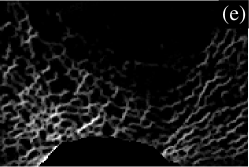

III.6 Illustration

To illustrate the analytical method, we now present the results in visual form for an enlarged region near the bottom (posterior) of the slice in Fig. 1. The enlarged region of the original image is shown in Fig. 3(a). Parts (b) to (e) of Fig. 3 show directional strand strengths, and part (f) shows the final node strength plot. Each directional strand strength plot shows the sum of two strand strengths at every pixel, in opposite directions: east/west; north/south; northwest/southeast; and northeast/southwest. In each of the directional strand strength plots, the strands in the given direction are shown with the highest intensity, but most of the trabeculae are still visible, even if faintly. In contrast, in the node strength plot (part (f)), most of the trabeculae are invisible. This is because of the subtraction of the minimum strength constant. In this example, there are almost no nodes in the right half of the image. This correctly describes the micro-architecture of the original image in that region, which contains many trabeculae but few that cross each other to make a lattice-like micro-architecture. The left half of the image contains many nodes. Notice that, in the node strength plot, the nodes seem to be thicker than in the original image. This is because the trabeculae in the original image are actually slightly thicker than they appear, the outer pixels being dimmer (i.e. lower CT values) and thus not easily registered by the eye. Since the outer pixels near the apparent nodes in the original image are almost as well-connected as pixels in the centres of the nodes, they have large node strengths, and are very visible in the node strength plot.